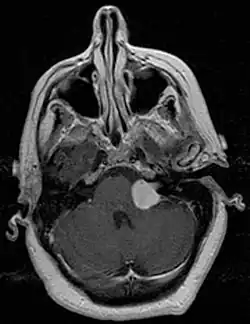

There have been cases of tumors that were actually asymptomatic until very large and at a critical stage. Tumor growth rates are highly variable: some small VSs (perhaps 50%) do not grow at all; some few grow for a time and then shrink; some appear dormant but suddenly grow rapidly. In general, although studies differ, VSs that grow are slow-growing at an average rate of 1.2 to 1.9 mm per year. IAC tumors that grow beyond 1.5 cm in diameter expand into the relatively empty space of the cerebellopontine angle, taking on the characteristic 'ice-cream-cone' appearance seen on MRIs. As 'space-occupying-lesions,' the tumors can reach 3 to 4 cm or more in size and infringe on the facial nerve (facial expression) and trigeminal nerve (facial sensation). Advanced hearing loss and spells of true vertigo may occur. Very large tumors are life-threatening when they press on the cerebellum or cause brainstem compression. Late symptoms of very large VS include headache, nausea, vomiting, sleepiness, mental confusion and eventually coma.[3][4]

MRI scan is the imaging of choice because it can more accurately differentiate the mass from other tumors such as meningioma, facial nerve schwannoma, epidermoid cyst, arachnoid cyst, aneurysm, and brain metastasis. MRI scan also helps in surgical planning and follow-up of the tumor after surgery.[19] VS is usually isointense on T1 weighted images, hyperintense on T2 weighted images, and enhances after given gadolinium contrast.[20]